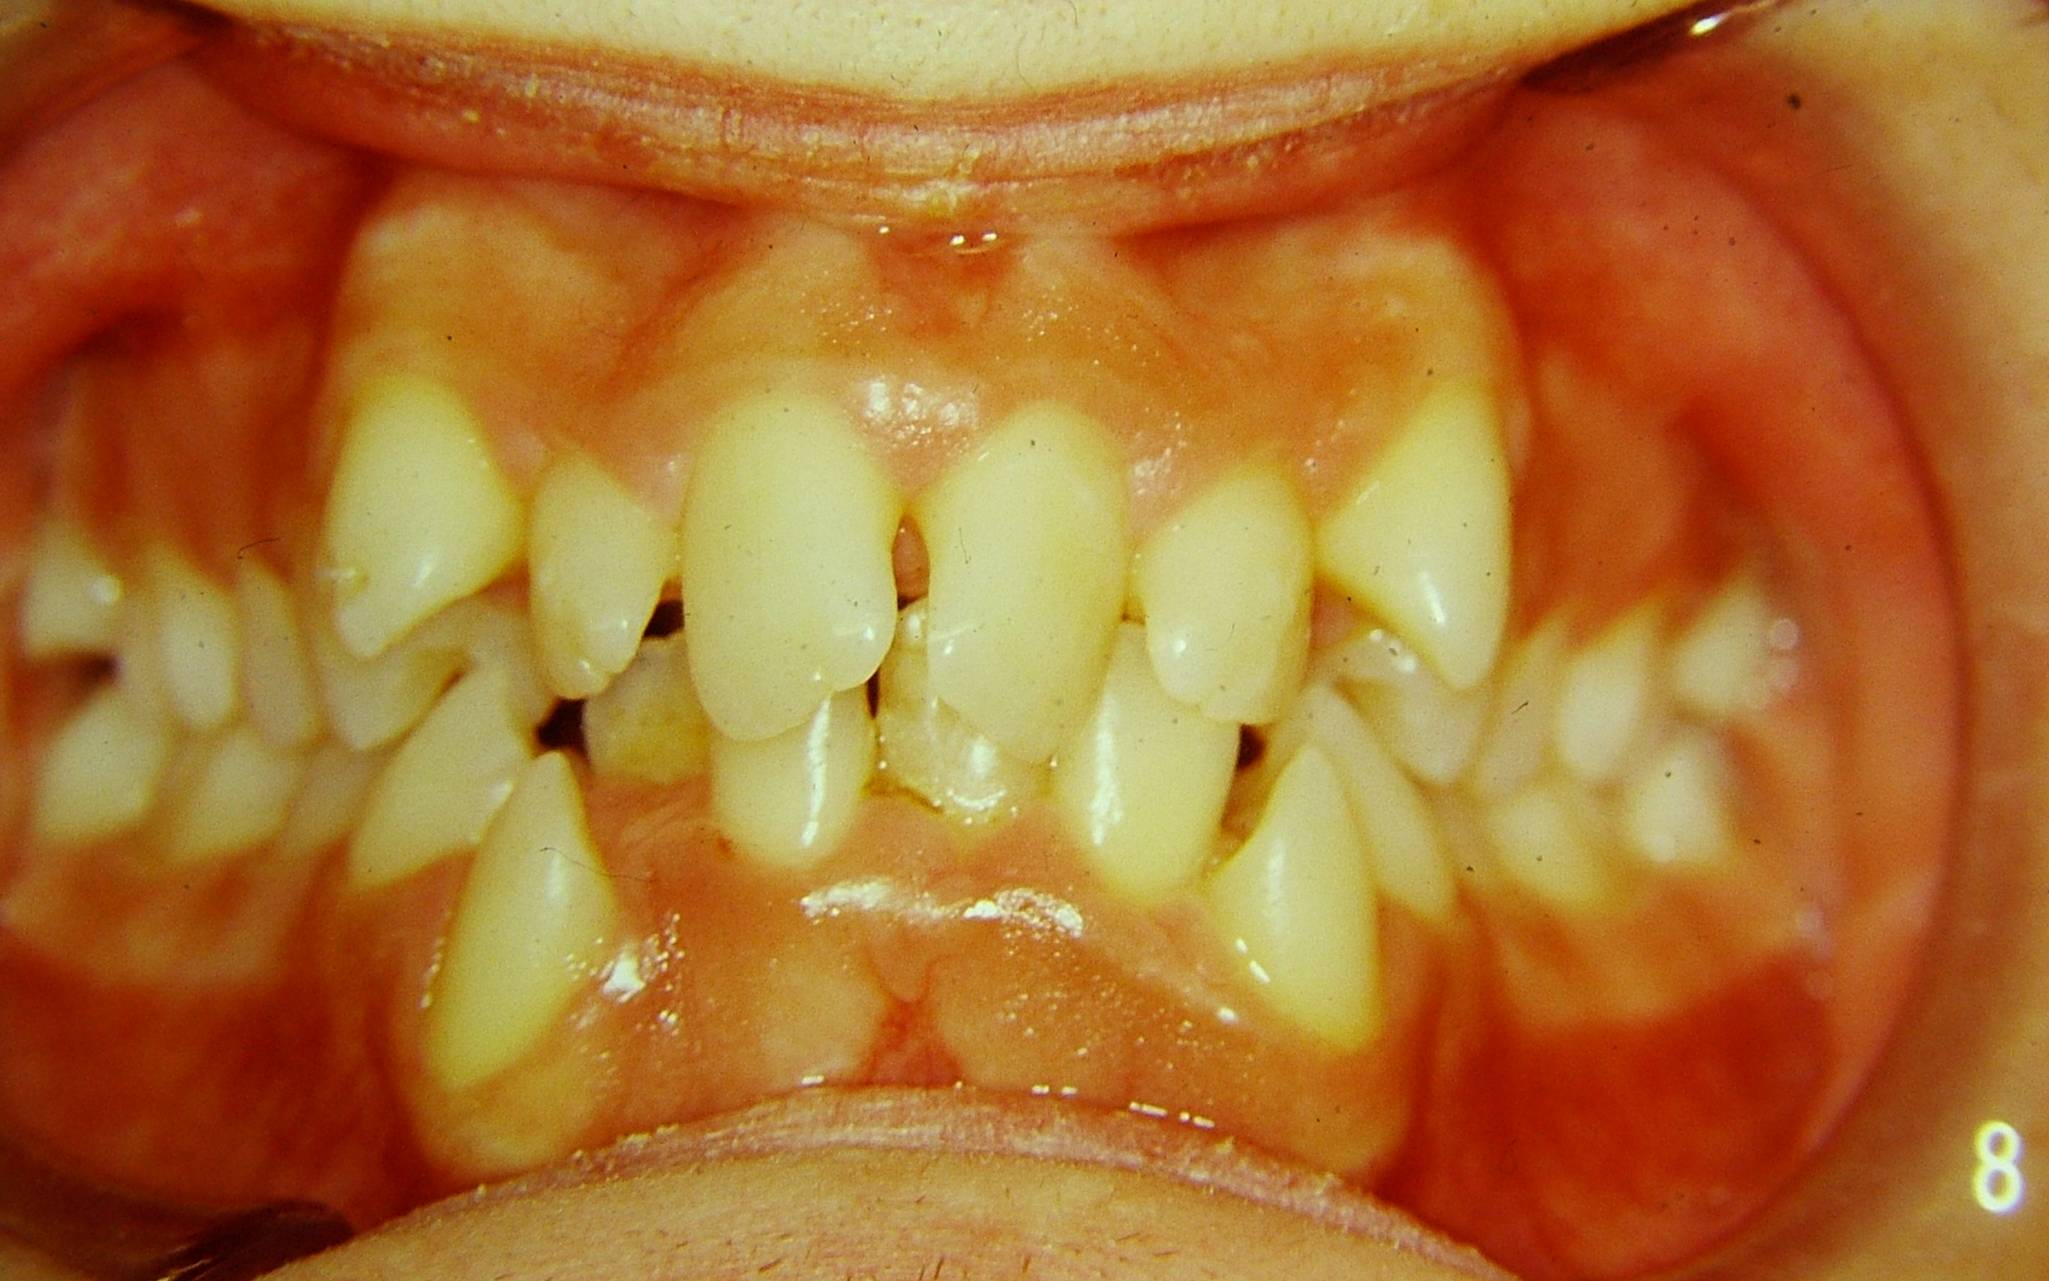

Caso impegnativo di grave affollamento in pz biprotruso che ha richiesto la estrazione di 14 24 34 44